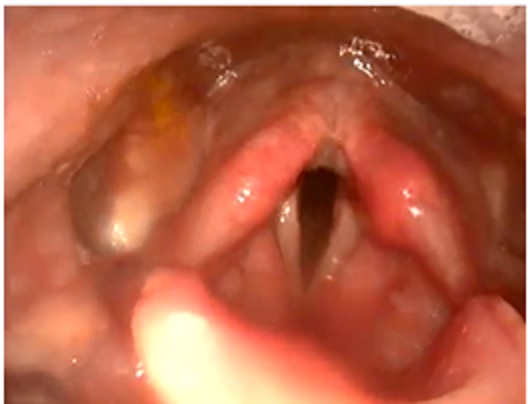

下圖為:在喉鏡下因為胃食道逆流所造成喉頭腫脹的情形

胃酸所引起厲害的喉頭腫脹 輕微的喉頭腫脹(左側>右側)